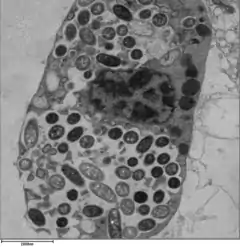

| Colorized scanning electron micrograph image of L. pneumophila | |